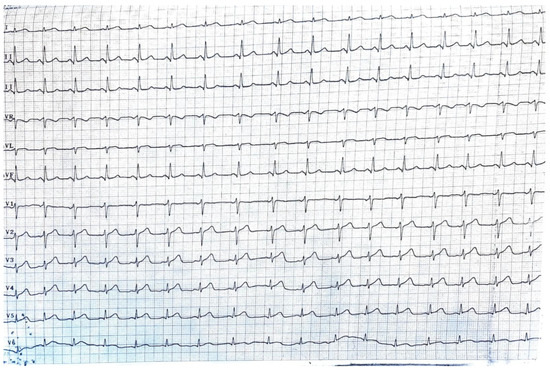

The peritoneal cancer index (PCI) [6] in this case was 14, suggesting a moderate degree of peritoneal surface involvement by the peritoneal carcinomatosis. The peritoneal cancer index (PCI) is a numerical score used during CRS to quantify the extent of disease in different regions of the abdomen and pelvis. With a PCI of 14, there is a moderate volume of disease present in various regions. The significance of this score depends on several factors, including the specific locations of tumor involvement, the type of cancer, and the overall health of the patient [7]. The cardiological evaluation prior to surgery revealed no significant cardiac comorbidities with no ventricular dilatation and an ejection fraction (EF) of 65%. No coronarography was requested, as the patient had no history of past cardiac events (Figure 3).

Figure 3.

The ECG of the patient at admission, showing no signs of modifications.

In the postoperative period, approximately 18 h after undergoing surgery for colonic cancer recurrence, the patient experienced an abrupt onset of cardiac arrest because of ventricular fibrillation. Immediate resuscitation measures, including cardiopulmonary resuscitation (CPR), defibrillation, and administration of vasoactive medications, were initiated. The multidisciplinary team, including cardiologists, intensivists, and oncologists, collaborated closely to manage the cardiac complications. Despite resuscitation efforts, the patient faced two instances of heart arrests, after which she developed severe bradycardia, before establishing normal sinus rhythm (Figure 4). The echocardiogram performed after the resuscitation showed an EF of 20% with akinesia of the medium and distal portion of the interventricular anterior septum, the apex, and the medium and distal portion of the lateral ventricular wall with hypokinesis of the ventricular base (an aspect highly suggestive of catecholamine-induced cardiomyopathy or takotsubo cardiomyopathy), moderate mitral regurgitation, acute pulmonary edema and a hypokinetic right ventricle, with no pleural effusion. There was a significant rise in cardiac enzymes.

Figure 4.

The ECG of the patient after CPR, showing no signs of modifications.